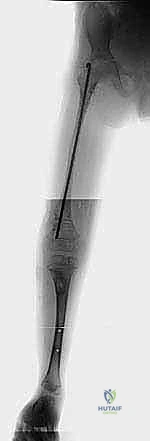

بعد التأكد من استقرار مفصل الورك والركبة، تبدأ مرحلة التطويل. يستخدم الدكتور هطيف أحدث التقنيات العالمية في صنعاء:

* المثبت الخارجي (Ilizarov / TSF): جهاز حلقي يثبت حول الساق، يتم من خلاله إجراء قطع عظمي دقيق (Corticotomy). يقوم الأهل بلف صواميل الجهاز يومياً بمقدار 1 ملم، مما يحفز الجسم على بناء عظم جديد في الفجوة (Distraction Osteogenesis).

* المسامير النخاعية المغناطيسية (Magnetic Internal Nails): في حالات معينة للأطفال الأكبر سناً، يمكن استخدام مسامير تزرع داخل العظم وتستطيل عن بعد باستخدام جهاز مغناطيسي خارجي، مما يقلل من خطر العدوى ويوفر راحة أكبر للمريض.

| المرحلة الثالثة | 4 - 6 سنوات | الجلسة الأولى لتطويل عظمة الفخذ (عادة من 5 إلى 8 سم). | تقليل الفارق في الطول، تحسين المشية، البدء في العلاج الطبيعي المكثف. |

| المرحلة الرابعة | 8 - 12 سنة | الجلسة الثانية للتطويل (الفخذ و/أو القصبة)، تصحيح أي انحرافات محورية جديدة. | مواكبة نمو الطفل السريع، الحفاظ على استقرار المفاصل. |